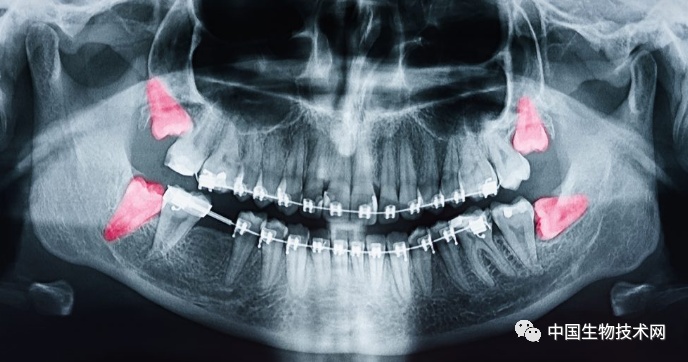

在人类近亲中,只有黑猩猩像我们一样会延长在关键发育期的时间。但即使是黑猩猩,也早早长齐了满口牙。而现代智人直到青春期结束才开始萌出第三磨牙,即阻生智齿(俗称智齿)。健康的智齿可以帮助咀嚼,但有问题的智齿可能会引起牙龈组织发炎和感染,最终导致冠周炎。所以,很多人不得不拔掉有问题的智齿。

我们用来把食物磨成糊状的成熟牙齿通常分三个阶段从口腔中萌出,即6岁、12岁和18岁左右。

其他灵长类动物的成年臼齿长得更早。像人类的近亲黑猩猩(Pan troglodytes)在3岁、6岁和12岁时都会长出臼齿。黄狒狒(Papio cynocephalus)在7岁时有了最后一颗成年臼齿;而恒河猴(Macaca mulatta)在6岁时就已经长出全部牙齿。

限制牙齿萌出时间的一个重要因素是空间。如果下颌不够大,就无法放下全套的成年牙齿,那么也就没必要把它们全都塞进去。

早期人类的口腔空间并不像现在这样大,阻生智齿(俗称智齿)是我们人类面临的一个主要问题。但这并不能解释为什么它们在我们的生命中出现得这么晚,或者为什么后面的那些智齿似乎总在制造麻烦。